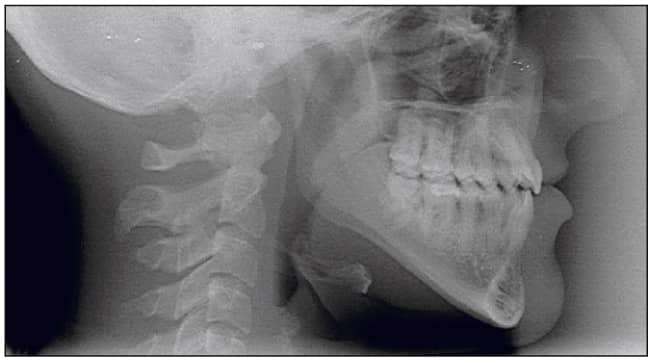

During the next 8 months of treatment, the occlusal plane was successfully reconstructed (tipped down in the front and steepened). Detailing ensured a stable functional occlusion. The patient was debonded and instructed to indefinitely wear an upper and lower thermoformed retainer a minimum of three nights per week (Figures 7 to 12).